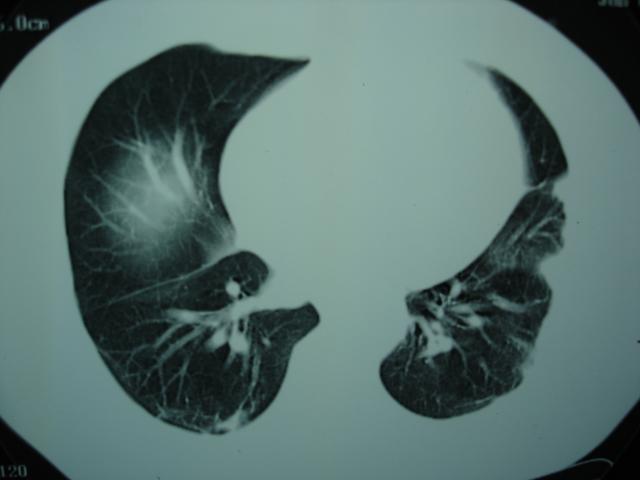

2009.6.4 2009.6.7 2009.8.21

第三次ct2009.8.21

病灶与胸膜成直边征,考虑炎症假瘤可能性大。

考虑左肺上叶炎症感染(炎性假瘤可能)。

考虑 左肺上叶炎症感染 [炎性假瘤可能性大]。

不排除肺癌

考虑左肺上叶炎症感染,以炎性假瘤可能性大。